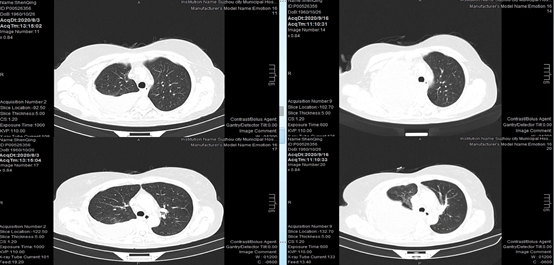

2020-05-07,患者复查过程中,发现胸腔积液进一步增多,胸膜下病灶进一步增大。随即调整治疗方案,予以奥希替尼80mg qd,再次胸腔闭式引流,胸水送检制作细胞蜡块,胸腔内注射恩度,予培美曲塞、卡铂化疗2周期。

2020-08-03,患者再次入院复查,发现胸膜下病灶较前缩小,胸腔积液也有一定好转,但持续存在。

2020-09-16,CT复查提示患者胸水进一步增多。